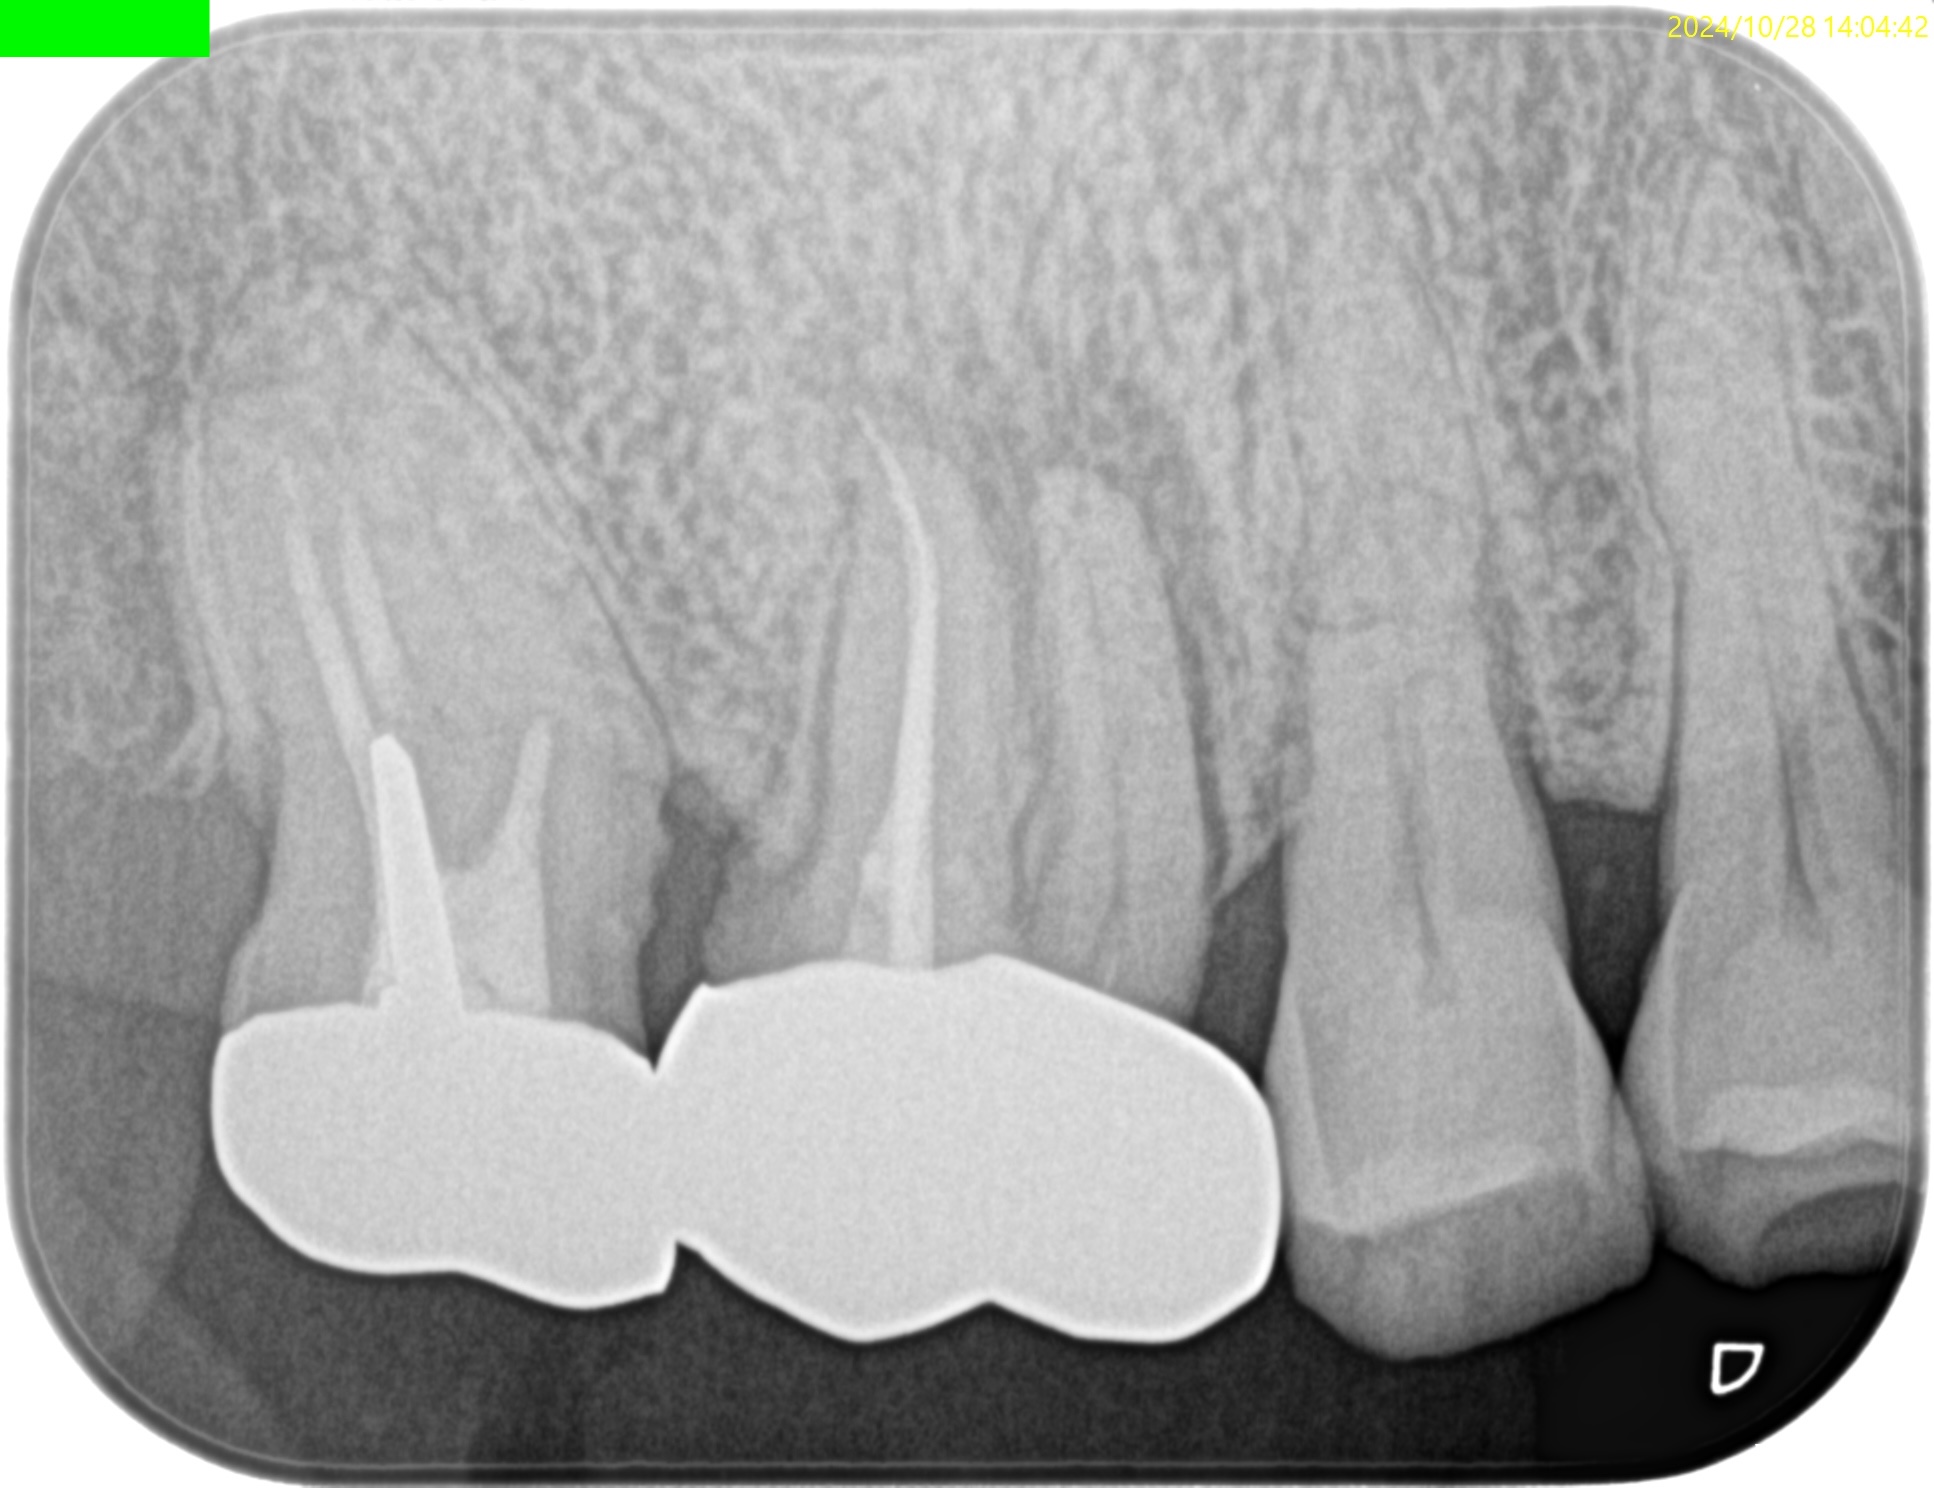

PA(2024.10.28)

Pre-op Endo Diagnosis(2024.10.28)

Pulp Dx: Normal Pulp Tissues

Periapical Dx: Symptomatic apical periodontitis

Recommended Tx: RCT